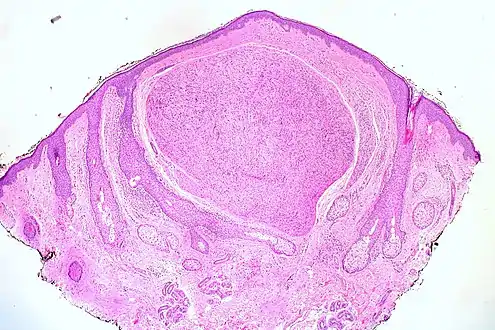

Micrograph of a palisaded encapsulated neuroma

Palisaded encapsulated neuroma (PEN) is a rare, benign cutaneous condition characterized by small, firm, non-pigmented nodules or papules.[1][2] They typically occur as a solitary (single) lesion near the mucocutaneous junction of the skin of the face, although they can occur elsewhere on the body.[3]

As mentioned previously, PEN is a benign, firm, flesh-coloured lesion that typically occurs in dermis of the skin of the face. The lesions are typically between 2–6mm and are slow-growing.[3][4]

PEN is diagnosed by clinical recognition of the lesion and on subsequent histologic examination. Typically, the lesions are suspected to be schwannomas or neurofibromas clinically with PEN being an incidental finding on histology.[3]

PEN is typically diagnosed in patients between the ages of 40 and 60 years and occurs more frequently in females than males. The diagnosis of PEN may be difficult, even with confirmatory histology, due to its histological similarities with schwannomas and neurofibromas. It is imperative that the correct diagnosis is made the misdiagnosis of a neurofibroma may lead to unnecessary further investigation into associated systemic syndromes such as neurofibromatosis type 1 or multiple endocrine neoplasia syndrome.[3][4]